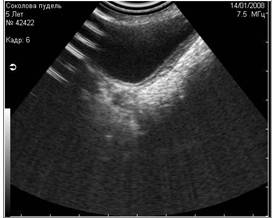

2. Дистальное затухание

При сканировании глубоко расположенных структур, получение качественного изображения затрудняется. Это связано с тем, что на глубоко расположенные структуры у ультразвукового луча остаётся мало энергии(4).

Рис. 6. Дистальное затухание. На снимке этот артефакт представлен тёмной полосой в дистальной части скана. Часто этот артефакт имитирует жидкостные структуры. |